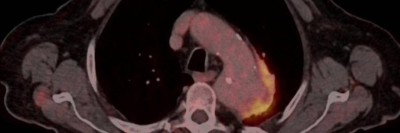

Wie hängen Aneurysma, Sepsis und Kolonkarzinom zusammen?

Ein 92-jähriger Mann stellt sich mit progredienter Dyspnoe, starken retrosternalen atemabhängigen Schmerzen und Fieber vor. Das Thorax-CT zeigt ein Aortenaneurysma mit einer Dissektion und periaortalem Gas. Liegt die Ursache in der Sepsis, die einige Monate zuvor aufgetreten ist – und wie ist die weitere Behandlung verlaufen?

Marginalvene Typ IV/© Gebhardt C et al. / all rights reserved Springer Medizin Verlag GmbH, OCT der Papille am linken Auge/© Jandewerth T et al. doi.org/10.1007/s00129-024-05289-9 unter CC-BY 4.0, Angiogramm bei Bauchaortenaneurysma/© Belezapoy / Stock.adobe.com, PET-CT Aortenaneurysma/© Novoa Usme M.M. et al. / all rights reserved Springer Medizin Verlag GmbH, Zerebrales Aneurysma/© Springer Medizin Verlag GmbH, Übergabe Notfallpatient vom Rettungsdienst an Notaufnahme/© andresr / Getty Images / iStock (Symbolbild mit Fotomodellen), Arzt übergibt Patient Medikamente/© joyfotoliakid / stock.adobe.com (Symbolbild mit Fotomodellen), Frau mit Tablette und Wasserglas in Händen/© fizkes / stock.adobe.com (Symbolbild mit Fotomodell), Operation/© Tobilander / stock.adobe.com (Symbolbild mit Fotomodellen), Blutdruck messen/© (M) sudok1 / stock.adobe.com, Ernährungssonde im Röntgenbild/© Klinischer Image- und Bilddokumentenfokus der Klinik für Radiologie und Nuklearmedizin; Otto-von-Guericke-Universität mit Universitätsklinikum, Magdeburg, Deutschland, Search Icon, Die Leitlinien für Ärztinnen und Ärzte, Darmpolypen/© Hollenbach M et al. / all rights reserved Springer Medizin Verlag GmbH, Arzt erläutert Mammographie-Befund/© Gorodenkoff / stock.adobe.com (Symbolbild mit Fotomodell), Box mit Tabletten/© ekachai050050 / stock.adobe.com (Symbolbild), Blutabnahme/© Grafvision / stock.adobe.com (Symbolbild mit Fotomodellen)